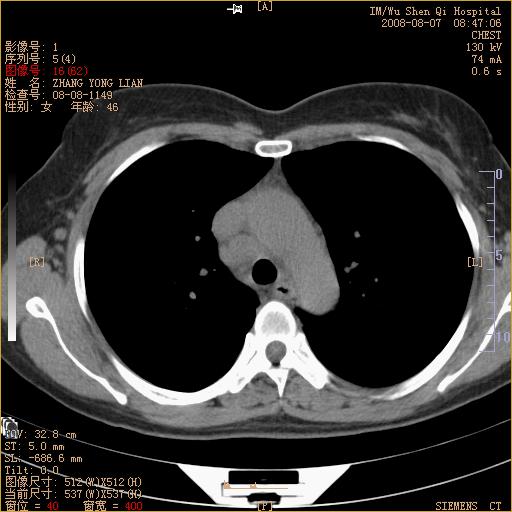

标题: CT15050:女,46岁,咳嗽胸痛一月余 [打印本页]

标题: CT15050:女,46岁,咳嗽胸痛一月余

纵隔窗没发全,左下肺近胸膜处结节。有长毛刺,纵隔淋巴结增大,不排除恶性病变。

考虑左肺下叶后基底段周围型肺癌伴纵隔淋巴结转移可能性大。

左下肺ca并纵隔及左肺门区淋巴结转移。

脾脏低密度结节转移不排除。

1)考虑左肺下叶后基底段周围型肺癌伴纵隔淋巴结转移。2)脾内低密度灶,性质待定;不排除转移瘤可能。